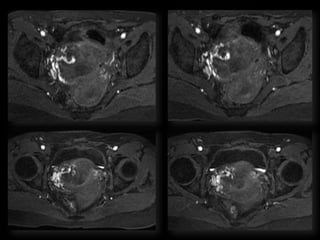

Dr. Hedvig Hricak

HISTORY

โ€ข   42 yo female

โ€ข   Recent immigrant from China

โ€ข   C/O postcoital and intermenstrual bleeding

โ€ข   Abnormal GYN exam

โ€ข   Abnormal biopsy

โ€ข   Further imaging performed

MRI findings - Stage IIB

with PET/CT - Stage IIIB

HISTORY โ€ข 42 yo female โ€ข Recent immigrant from China โ€ข C/O postcoital and intermenstrual bleeding โ€ข Abnormal GYN exam โ€ข Abnormal biopsy โ€ข Further imaging performed

• 63.

MRI findings -Stage IIB with PET/CT - Stage IIIB Cervical Cancer